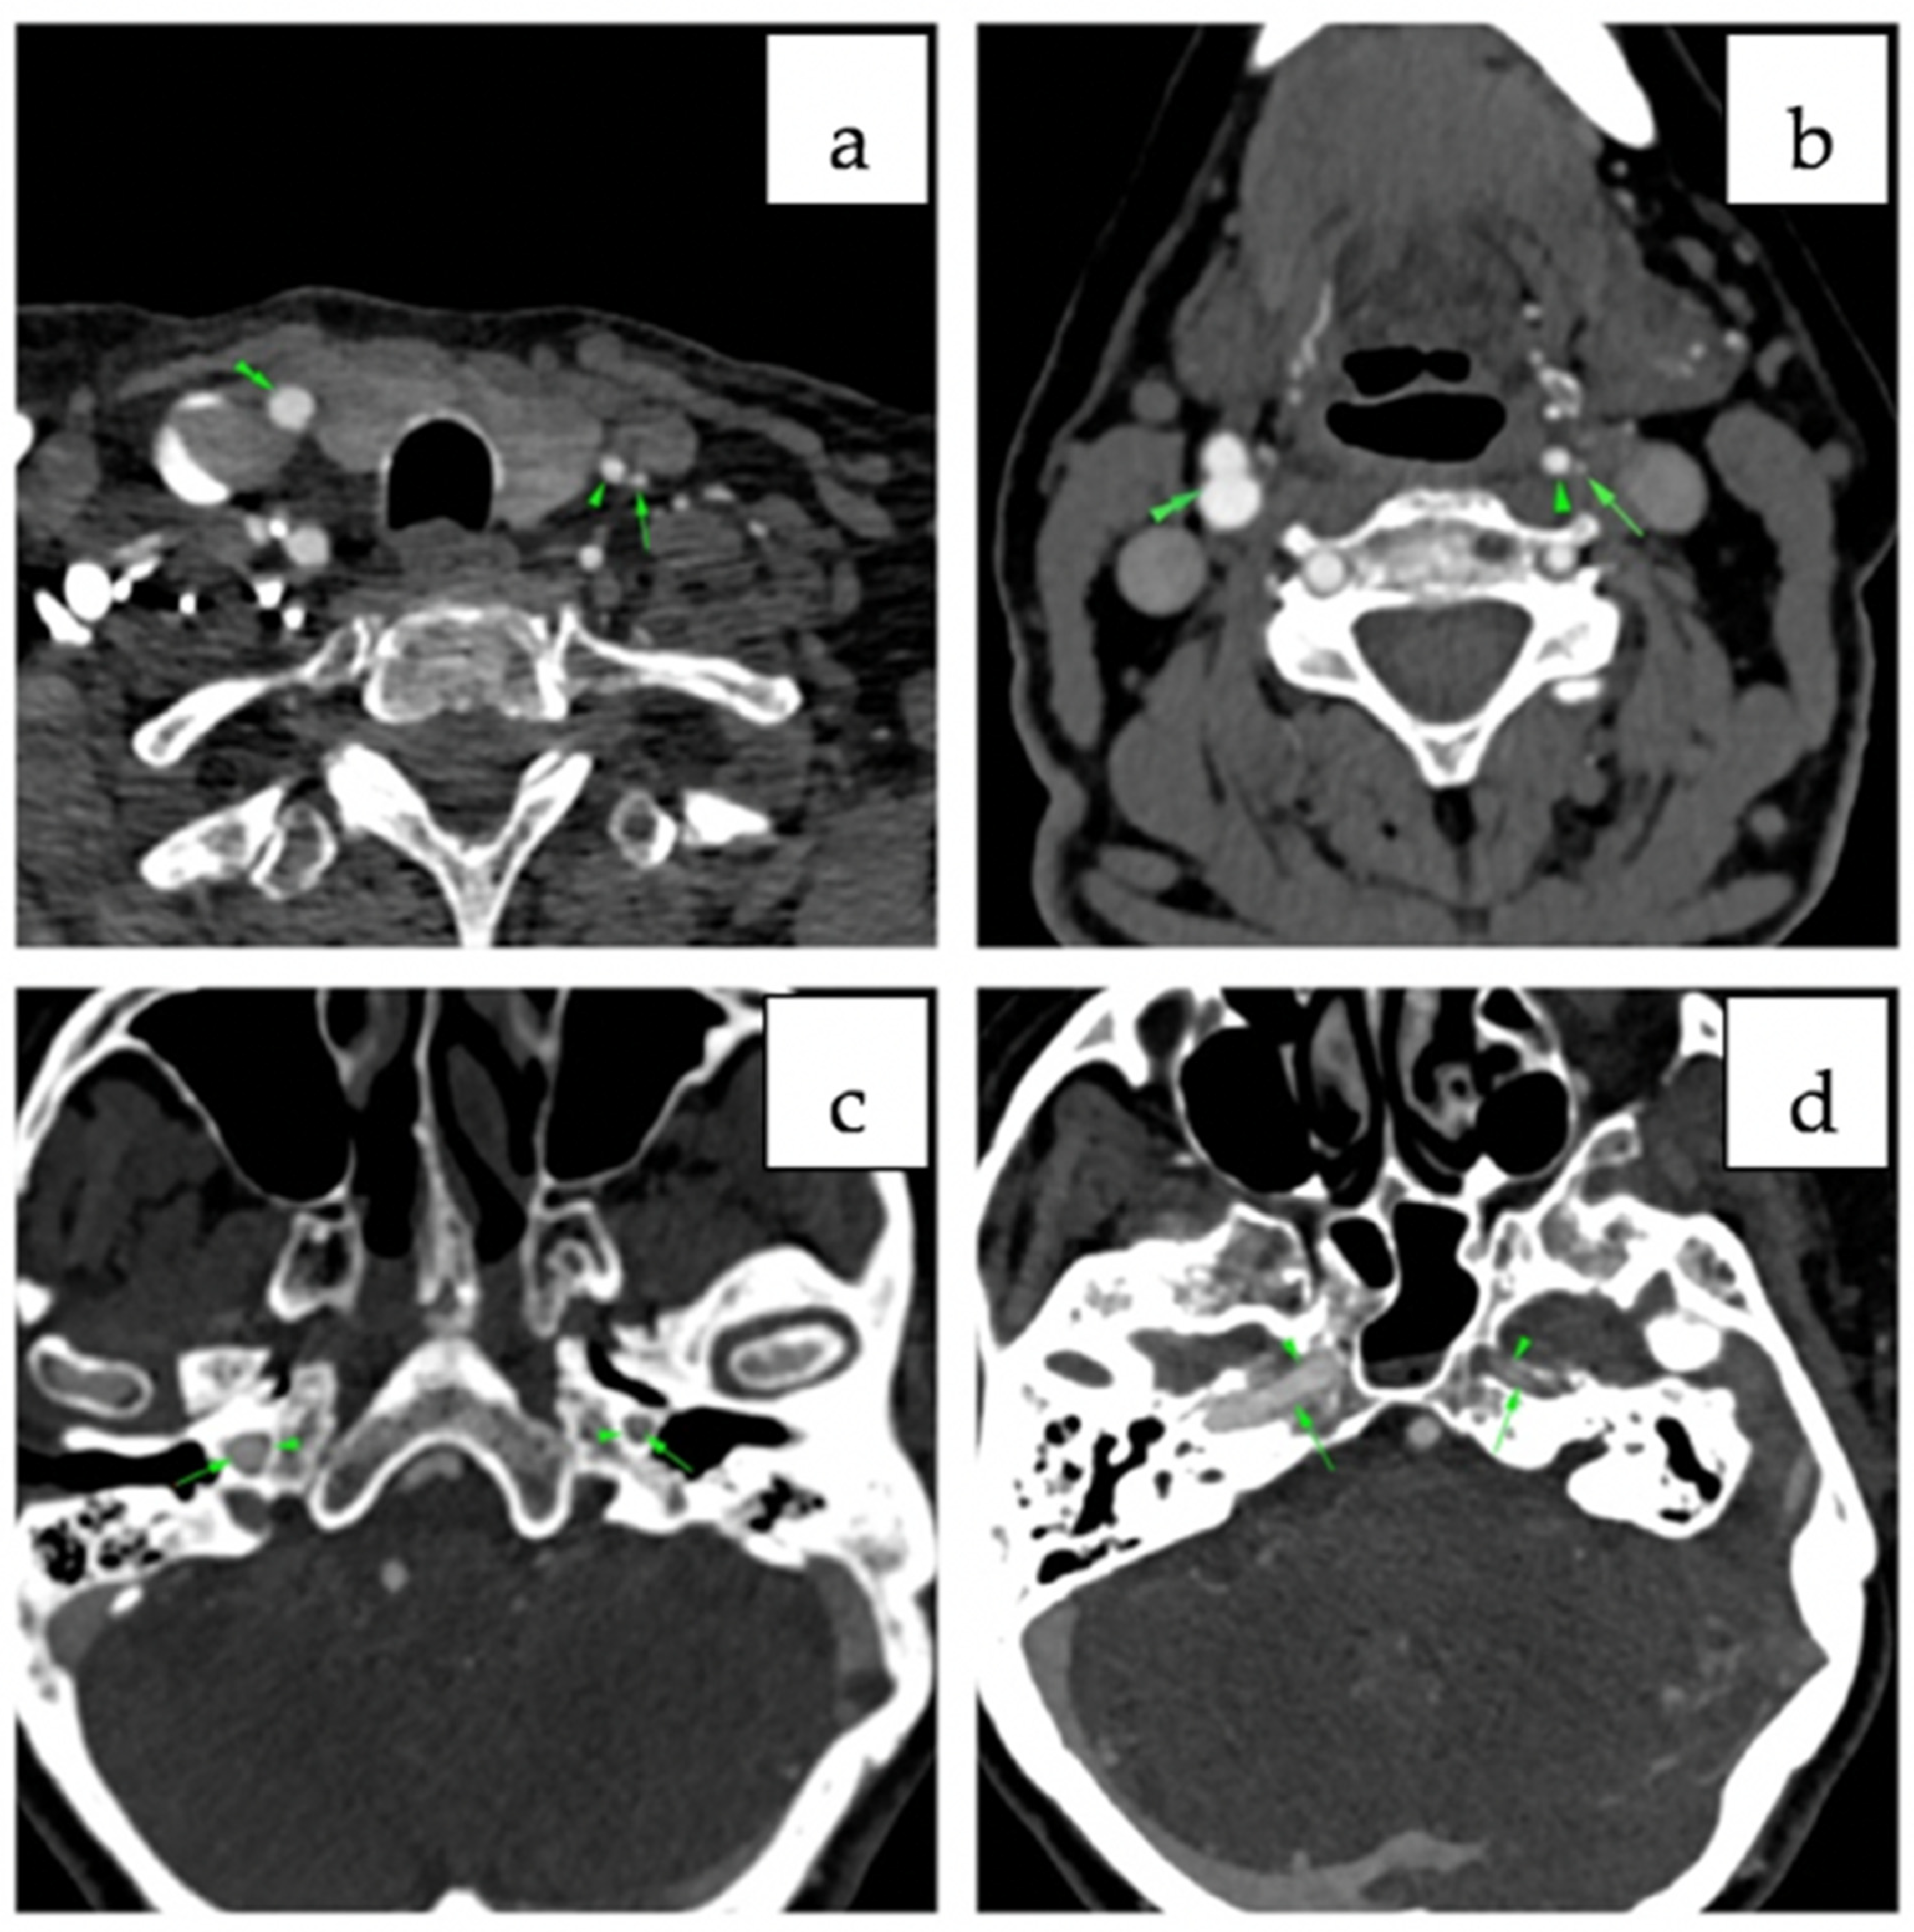

2. Case Report